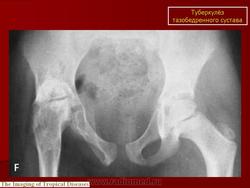

Туберкулез тазобедренного сустава (коксит)

Поражения тазобедренного сустава также относятся к одной из частых локализаций костно-суставного туберкулеза и на его долю приходится около 20% случаев поражений костей при туберкулезе. Если раньше считалось, что почти 60% случаев приходится на детей первого десятилетия жизни, то в настоящее время туберкулез тазобедренного сустава стал относительно часто встречаться у лиц старшего возраста.

При рентгенологическом исследовании в преартритической фазе самым ранним симптомом является остеопороз, который может быть незначительным и выявляться лишь на сравнительных рентгенограммах с захватом двух тазобедренных суставов. Еще до появления туберкулезного остита могут отмечаться изменения со стороны мягких тканей в виде увеличения теней межмышечных прослоек между контурами суставной сумки и малой и средней ягодичными мышцами (симптом Ланге - Будинова). Отмечается также асимметрия костей малого таза (симптом Пинхасика), обусловленная неправильным положением больного из-за атрофии мышц, или наоборот утолщением сустава на больной стороне, или вследствие болевой контрактуры. Зная наиболее частую локализацию туберкулезных оститов вокруг тазобедренного сустава можно выявить участки нарушения костной структуры, нечеткость костных трабекул. Спустя 1,5-2 месяца выявляются очаги деструкции костной ткани с нечеткими неровными контурами, которые могут содержать множественные губчатые секвестры. Наиболее часто туберкулезные оститы располагаются в костях, образующих вертлужную впадину, реже они встречаются в шейке, и как исключение в головке бедренной кости. Причем очаги деструкции костной ткани, расположенные в вертлужной впадине, лучше выявляются на задних рентгенограммах, а очаги деструкции в шейке бедра, особенно в нижне-внутреннем отделе ее лучше выявляется на рентгенограммах с отведением бедра (по Лауенштейну). У некоторых больных наблюдается ранняя деформация ядра окостенения головки бедра в виде его увеличения.

Артритическая фаза (при переходе процесса на сустав) на рентгенограммах характеризуется усилением остеопороза, который постепенно распространяется на все кости нижней конечности. Суставная щель асимметрично суживается, больше в верхне-наружных отделах. В дальнейшем сужение суставной щели достигает значительной степени. Суставные поверхности костей теряют свои очертания, их контуры становятся нечеткими, неровными. Выявляются краевые, без четких контуров содержащие секвестры, очаги деструкции костной ткани. Последние могут вызывать значительные разрушения вертлужной впадины, головки и даже шейки бедренной кости, смещение головки бедра вверх.

Стадия затихания характеризуется появлением четких контуров очагов деструкции в вертлужной впадине и в головке бедра, затем ободка склероза вокруг них. Остеопороз уменьшается. Появляются признаки репаративных процессов в виде толстых, расположенных вдоль силовых линий костных балок и уплотнение, склерозирование замыкательных пластинок. Могут выявиться в мягких тканях остаточные натечные абсцессы в виде более или менее плотных теней с признаками обызвествления. Остаточные каверны определяются в виде очагов деструкции костной ткани с достаточно четкими контурами и зоной реактивного склероза вокруг, с секвестрами в центре.